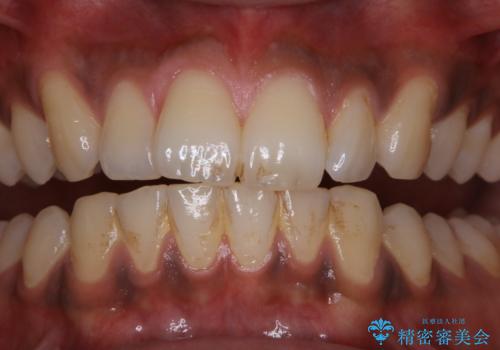

他人から口臭を指摘されて初めてのPMTC

- 他人から口臭を指摘されたので歯のクリーニング希望との事でした。

PMTC60分コースを行いました。

PMTCとはProfessinnal Mechanical Tooth Cleaning・専門器具による歯の機械的な清掃です。

バイオフィルム(細菌の塊)を破壊し、歯の表面をツルツルにすることでお口の中の細菌数を減らし歯周病のリスクが定着するのを防ぎます。更に、歯に新しい汚れがつきにくい状態になります。

PMTCを行うことにより、虫歯・歯周病・口臭予防だけでなくスッキリと爽快感が得られたり、見た目も清潔感のある状態になるため、今後の治療などお口に対するモチベーションUPにも繋がります。